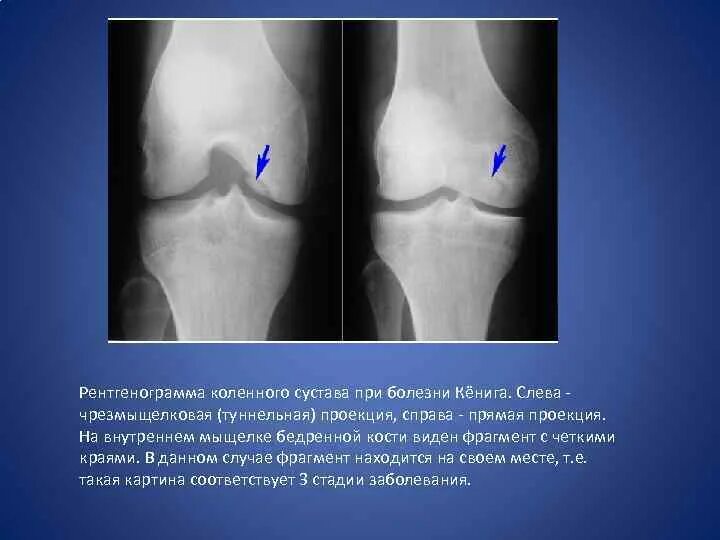

Повреждение хряща по outerbridge